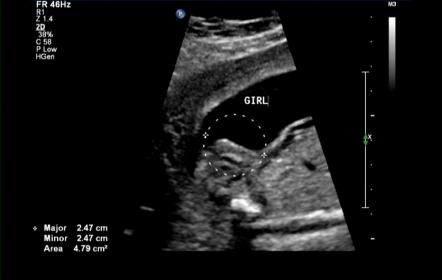

Attachment 7658 20 week nub shot